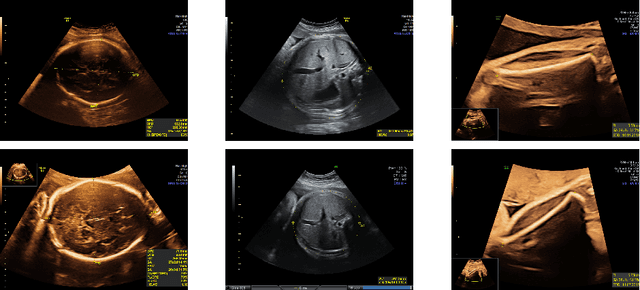

Abstract:Confounding information in the form of text or markings embedded in medical images can severely affect the training of diagnostic deep learning algorithms. However, data collected for clinical purposes often have such markings embedded in them. In dermatology, known examples include drawings or rulers that are overrepresented in images of malignant lesions. In this paper, we encounter text and calipers placed on the images found in national databases containing fetal screening ultrasound scans, which correlate with standard planes to be predicted. In order to utilize the vast amounts of data available in these databases, we develop and validate a series of methods for minimizing the confounding effects of embedded text and calipers on deep learning algorithms designed for ultrasound, using standard plane classification as a test case.